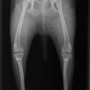

■ 症例22 ポメラニアン 1歳5か月 去勢雄

左後肢の挙上を主訴に来院した。整形学的検査、レントゲン検査より左右の膝蓋骨脱臼(左GradeⅡ〜Ⅲ、右Grade Ⅱ)を認めた。また、脛骨の前方引き出し試験の際に、引き出し兆候は認められないものの、疼痛が認められたため、前十字靭帯の損傷が疑われた。術中における、目視および関節内の操作によって、前十字靭帯の損傷や過伸展といった異常が認められなかったため、膝蓋骨脱臼の整復のみ実施した。手術手技は縫工筋及び内側広筋の解放、脛骨粗面の外側転位、滑車ブロック形造溝術、内外側関節包の縫縮を実施した。本症例は跛行もなく経過良好である。しかし、頸骨高平部の角度(TPA)が 右26.2°、左24.9°であり、解剖学的に前十字靭帯損傷のリスクが高いことから今後の経過に注意が必要である。